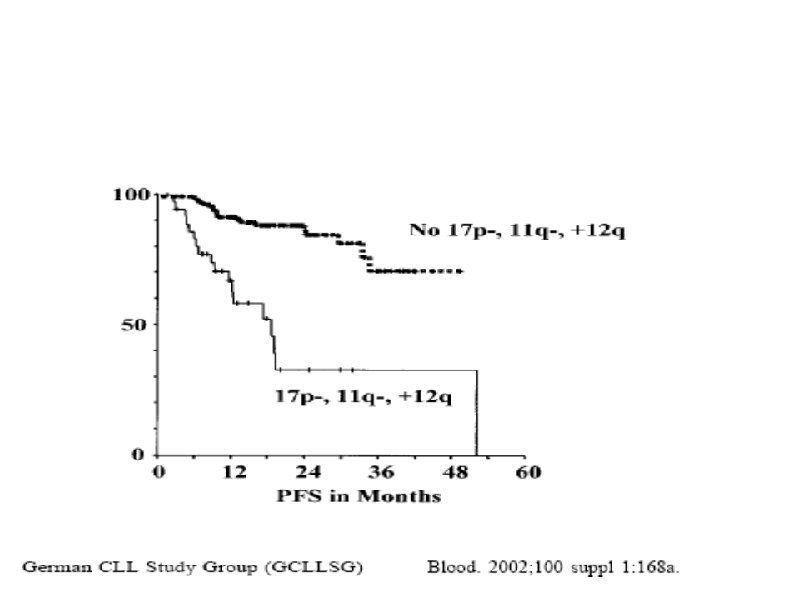

Время удвоения лимфоцитов менее 6 месяцев Время удвоения лимфоцитов более 6 месяцев Стадия на момент диагноза III – IV / C (Rai / Binnet) Возраст менее 65 лет I – II / A Возраст более 65 лет ZAP-70 < 20% Соматическая мутация (-) Соматическая мутация (+) 17 p делеция (p 53 мутация), 13 q делеция 11 q делеция, 12 q трисомия CD 38 (+) CD 38 (-)